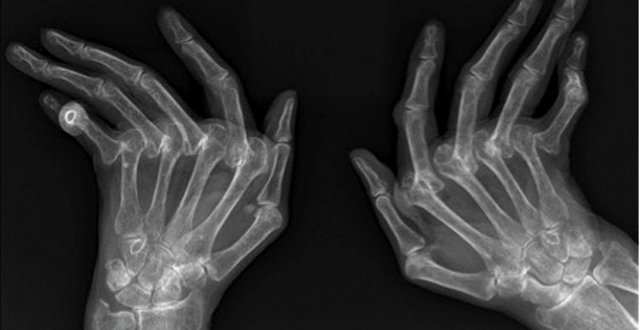

Psoriatic arthritis (PsA) is a chronic inflammatory disease of the musculoskeletal system that, like rheumatoid arthritis (RA), can lead to joint damage, deformity, functional impairment and disability.

However, PsA is a distinct entity from RA, with a differing pattern and distribution of peripheral and axial joint involvement in the majority of cases. Unlike RA, PsA is associated with psoriasis, dactylitis and enthesitis, features of spondyloarthropathy (SpA); up to 30 per cent of patients with psoriasis have evidence of PsA.

The aim of modern treatment of PsA is to prevent joint damage, thereby preserving joint function and patient independence. Joint damage in PsA manifests radiographically as articular erosion and/or ankylosis of affected joints, which will be seen clinically as reduction in the normal range of movement of the joint and physical deformity. As joint damage can proceed rapidly after the onset of symptoms, it is imperative that assessing clinicians have a high index of suspicion in patients with psoriasis presenting with joint and/or musculoskeletal complaints.